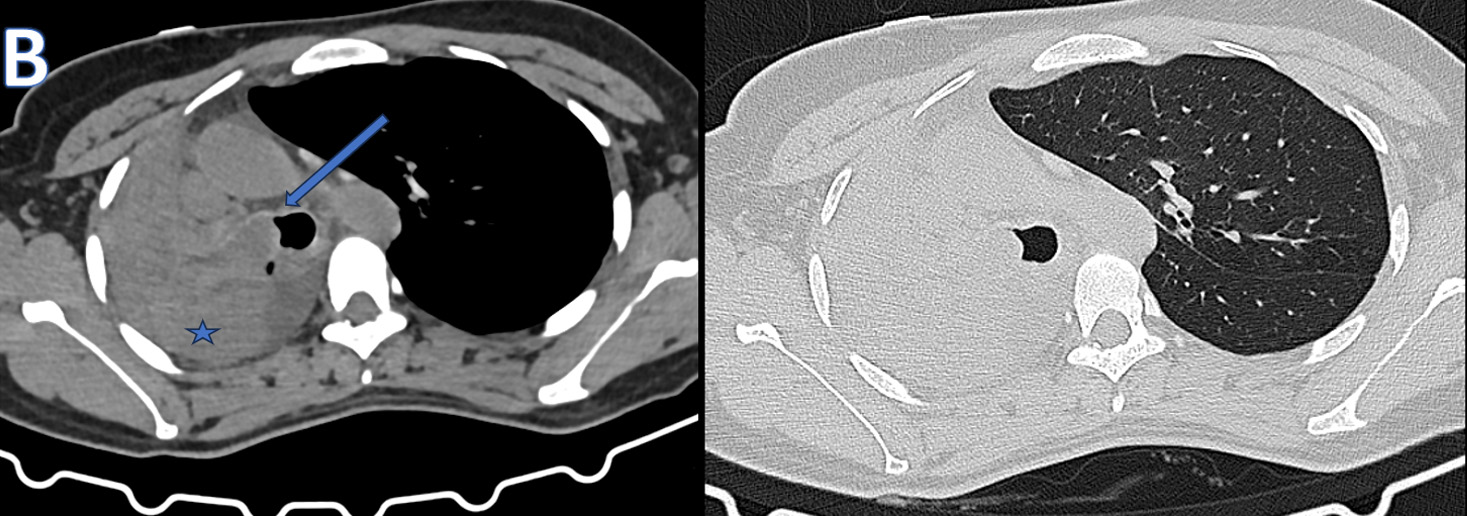

D – Axial CT Thorax

• ARROW:  Isodense mass lesion with peripheral calcific specks and endobronchial extension.

• STAR: Organised / Clotted - Hemorrhagic contents in the right hemithorax.